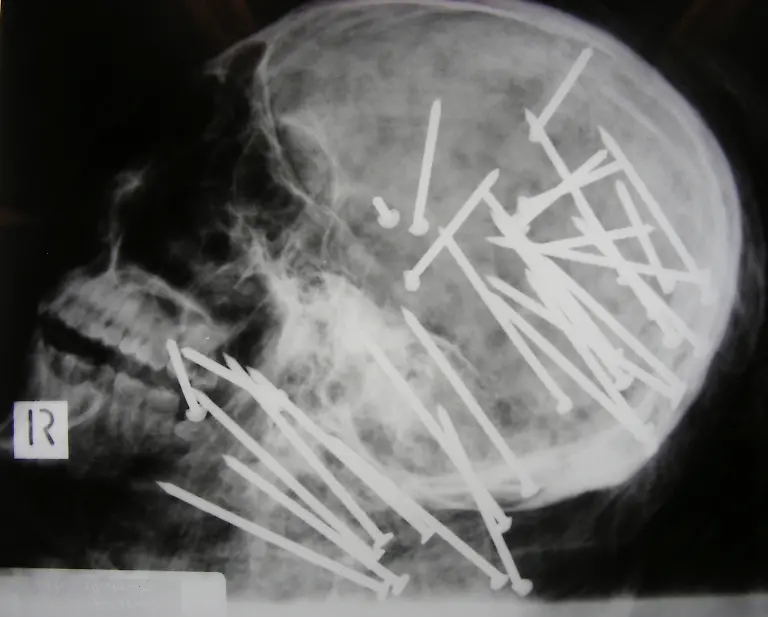

Nägel, Messer, TelefoneWas Röntgenstrahlen zum Vorschein bringen

Nicht immer zeigen Röntgenaufnahmen das, was man von ihnen erwartet. Oft kommt es zu Bildern, die selbst hartgesottene Betrachter zum Schaudern bringen - und der Wissenschaft Rätsel aufgeben.